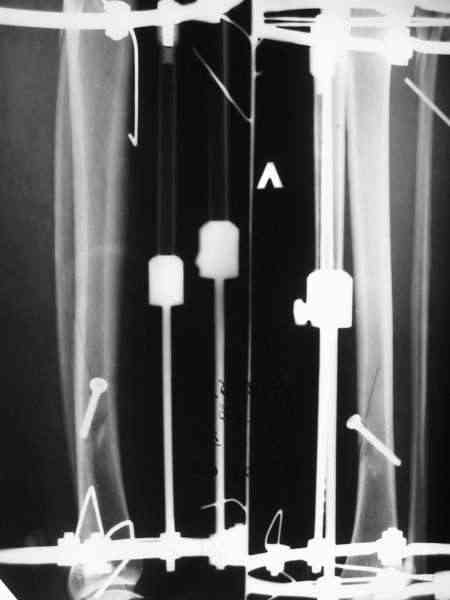

Вроде как раз удалось суммировать достоинства обоих методов, и минимизировать их недостатки. Аппарат - минимальный, то есть время/силы сэкономили, мышцы сильно не прошили, проблем с разработкой не будет, нагружать можно, при необходимости можно напрячь на дистракцию или компрессию. Внутренняя фиксация - и малоинвазивная (особенно если закрыто делать), и недорого, и нет массивных имплантатов, отслойки тканей. Если не срастется, в отличие от несращения на пластине, удалить один винт всего надо, и аппарат уже есть. В общем, дешево и сердито.

Там не просто "всего 1 пара колец" - там еще и компрессирующий винт, который выполняет функцию спиц с встречными упорами. Эти два кольца могут быть на начальном этапе лечения напряжены на дистракцию, так что могут противостоять большим осевым нагрузкам.

Мы лет 5-6 назад, когда еще не делали закрытое штифтование, сделали с десяток подобных операций, в том числе несколько на бедре. Репозиция закрытая, кортикальный винт 4,5 мм через прокол. Ближний кортекс рассверливали до 5 мм после нарезания резьбы, то есть получался нормальный компрессирующий винт. Аппараты только уже делали монолатеральные стержневые, чтобы не прошивать насквозь мышцы спицами (пример в приложении).

Хотя, конечно, вполне можно и обычные кольца со

спицами.